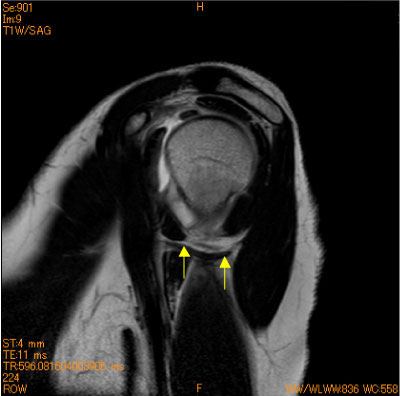

HAGL(humeral avulsion glenohumeral ligament)

40代女性。反復性脱臼肩、スキー歴(+)。

中高年の症例では、腱板断裂やHAGL(humeral avulsion glenohumeral ligament)の有無をcheckする必要(+)

![]() Obl. Sag T2WI |